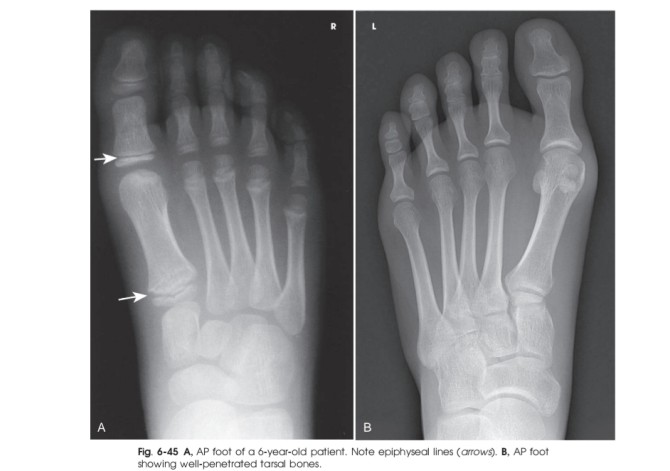

رادیوگرافی ها ممکن است با اشعه مرکزی عمود بر صفحه IR یا زاویه دهی 10 درجه به سمت خلف ( به سمت پاشنه ) بدست آید . زمانی که زاویه ی 10 درجه به سمت خلف استفاده می شود ، اشعه مرکزی عمود بر متاتارس ها و کوتاه شدگی کاهش می یابد .همچنین فضای مفصل TMT در ناحیه ی میانی کف پا بهتر نشان داده می شوند . ( تصاویر 6-39,6-40)